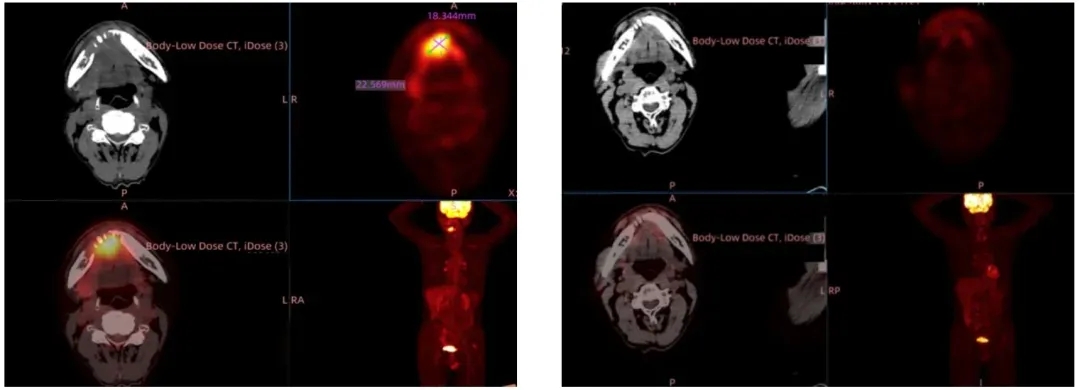

除ASCO公布的最新数据外,GT201联合PD-1抑制剂治疗晚期头颈部鳞癌的单臂临床研究,也在上海九院取得亮眼成果——首例口腔癌受试者已实现完全缓解。该受试者为61岁男性,2016年因喉癌接受手术及辅助放化疗后治愈,2023年9月确诊口底癌(属头颈部鳞癌,伴下颌骨侵袭及颈部多发淋巴转移)。因手术可能导致严重语言、吞咽功能障碍及外形损伤,患者放弃手术,且多轮化疗、靶向治疗后肿瘤仍快速进展,最终入组接受GT201治疗(配合桥接治疗及后续维持治疗)。

治疗结果显示:TIL输注后仅3周,患者病灶显著缩小达到部分缓解(PR);治疗9周随访时,影像学评估显示所有病灶完全消失,成功实现完全缓解(CR)(详见下图)。

▲图源“上海九院官网”,版权归原作者所有,如无意中侵犯了知识产权,请联系我们删除